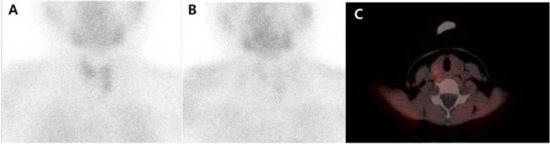

Role of 11C-Methionine PET/CT in 99mTc-Sestamibi-Negative Parathyroid Adenoma: A Case Report

- Braeuning, U.; Pfannenberg, C.; Gallwitz, B.; Teichmann, R.; Mueller, M.; Dittmann, H.; Reimold, M.; Bares, R. 11C-methionine PET/CT after inconclusive 99mTc-MIBI-SPECT/CT for localisation of parathyroid adenomas in primary hyperparathyroidism. Nuklearmedizin 2015, 54, 26–30. [Google Scholar] [CrossRef] [PubMed]

- Noltes, M.E.; Coester, A.M.; van der Horst-Schrivers, A.N.; Dorgelo, B.; Jansen, L.; Noordzij, W.; Lemstra, C.; Brouwers, A.H.; Kruijff, S. Localization of parathyroid adenomas using 11C-methionine PET after prior inconclusive imaging. Langenbecks Arch. Surg. 2017, 402, 1109–1117. [Google Scholar] [CrossRef] [PubMed]

- Lenschow, C.; Gassmann, P.; Wenning, C.; Senninger, N.; Colombo-Benkmann, M. Preoperative 11C-Methionine PET/CT enables focused parathyroidectomy in MIBI-SPECT negative parathyroid adenoma. World J. Surg. 2015, 37, 1750–1757. [Google Scholar] [CrossRef] [PubMed]

- Traub-Weidinger, T.; Mayerhoefer, M.E.; Koperek, O.; Mitterhauser, M.; Duan, H.; Karanikas, G.; Niederle, B.; Hoffmann, M. 11C-methionine PET/CT imaging of 99mTc-MIBI-SPECT/CT-negative patients with primary hyperparathyroidism and previous neck surgery. J. Clin. Endocrinol. Metab. 2014, 99, 4199–4205. [Google Scholar] [CrossRef] [PubMed][Green Version]

- Yuan, L.; Liu, J.; Kan, Y.; Yang, J.; Wang, X. The diagnostic value of 11C-methionine PET in hyperparathyroidism with negative 99mTc-MIBI SPECT: A meta-analysis. Acta Radiol. 2017, 58, 558–564. [Google Scholar] [PubMed]